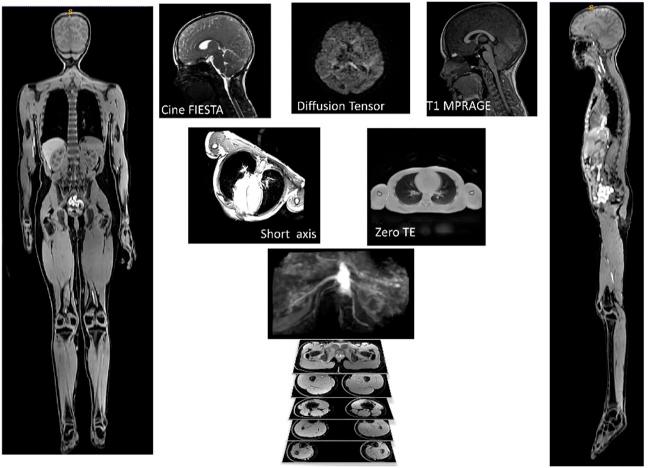

Roadmap for an imaging and modelling paediatric study in rural NZ.

Our study methodology is motivated from three disparate needs: one, imaging studies have existed in silo and study organs but not across organ systems; two, there are gaps in our understanding of paediatric structure and function; three, lack of representative data in New Zealand. Our research aims to address these issues in part, through the combination of magnetic resonance imaging, advanced image processing algorithms and computational modelling. Our study demonstrated the need to take an organ-system approach and scan multiple organs on the same child. We have pilot tested an imaging protocol to be minimally disruptive to the children and demonstrated state-of-the-art image processing and personalized computational models using the imaging data. Our imaging protocol spans brain, lungs, heart, muscle, bones, abdominal and vascular systems. Our initial set of results demonstrated child-specific measurements on one dataset. This work is novel and interesting as we have run multiple computational physiology workflows to generate personalized computational models. Our proposed work is the first step towards achieving the integration of imaging and modelling improving our understanding of the human body in paediatric health and disease.